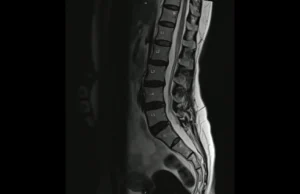

Resonancia magnética abierta de columna

La resonancia magnética abierta de columna se ha consolidado como una herramienta esencial en el diagnóstico y tratamiento de diversas patologías vertebrales. Este procedimiento no solo proporciona imágenes de alta calidad de las diferentes secciones de la columna, sino que también mejora la comodidad del paciente, haciendo que el proceso sea menos estresante y más … Sigue leyendo Resonancia magnética abierta de columna